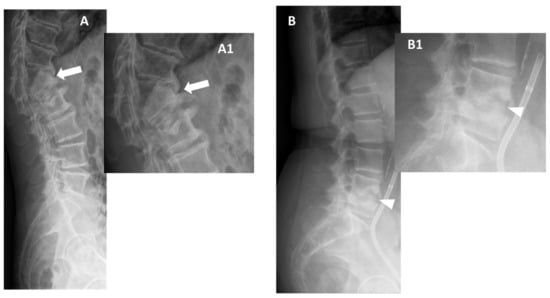

Figure 6. Tubercular spondylodiscitis. A 24-year-old man of Sudanese origin presented with thoracic and lumbar pain evolving for several months. An MRI was performed with (A) T2-weighted imaging (WI) and (B) contrast-enhanced (CE) T1-WI, as well as a CT-scan in bone kernel (C) and abdominal kernel after contrast medium injection (D,E). It demonstrates preserved disk but extensive sub ligamentous collections spreading along the anterior side of the thoracic and lumbar vertebral bodies (white arrowhead), but also along the posterior vertebral collateral ligament (white arrows) with large anterior and posterior erosions (black arrows). Please note the extensive collections spreading in the presacral space and along bilateral iliopsoas muscles without surrounding inflammation (white dashed arrows).

In Figure 6 an exemplificative case of TbS is presented.

Two features are especially correlated with TbS in almost all studies, namely thoracic involvement and the presence of more than two vertebral elements affected with multiple and non-adjacent vertebral bodies involved (skip lesions). Usually, the infection starts in the anterior subchondral region of the vertebral body and spreads frequently to the anterior longitudinal ligament and other subligamentous areas [53]. Involvement of posterior elements is also more common in this type of spondylodiscitis, even if the vertebral bodies are more frequently affected than the posterior arches [49,50,56]. Especially when there is relative disc preservation, posterior lesions need to be differentiated from neoplastic ones. In this setting, it may be useful considering that tubercular infections classically spread to soft tissue and adjacent ligaments in an anterolateral direction [50].

Virtually all studies have found well-defined paraspinal abnormal signal intensity with intraosseous, epidural, and paraspinal abscesses more frequently in TbS [49,50,51,52,53,54,55,56]. Thin and smooth enhancement of the abscess wall is one of the most reliable MRI findings of TbS (with possible calcifications), whereas ill-defined paraspinal abnormal signal and thick and irregular enhancement of the wall abscess are suggestive of PyS [50,51,52,53]. The chronic course, the relative late phase of TbS and the very minimal inflammation of these types of abscesses (named ‘cold abscesses’) are probably associated with this typical appearance of the abscess wall. Thus, contrast-enhanced infusion is necessary to differentiate these two kinds of spondylodiscitis [51,52,53,54].

The size of the paravertebral abscesses is also usually significantly larger in TbS than in PyS and they are often symmetrical. A psoas abscess was found to be a typical feature of this type of spinal infection [53]. The epidural abscess is also significantly more common in TbS and associated with a higher frequency of nerve and spinal cord compression [54,55,56]. Frel et al. showed that meningeal enhancement at the level of the pathological spinal segment was strongly associated with TbS [57,58].

Patients with PyS have limited vertebral injury, and most pathologic alterations are limited to the end plate. On the other hand, in TbS, more than half of vertebral bodies are involved, and they are frequently severely damaged. Vertebral loss of height and collapse with kyphosis (with possible spinal cold injury) most frequently occur in TbS in the thoracic spine and are generally seen in the later stages of tuberculosis [53,55]. Thus, large geodes, bone scalloping, sequestrum, vertebral fragmentation, and ivory vertebra (due to sclerosing response to osteonecrosis) are more typical of TbS compared to PyS.